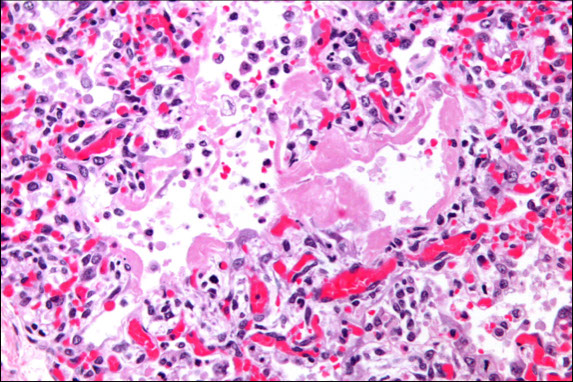

Diffuse Alveolar Damage

Hyaline Membrane in DAD